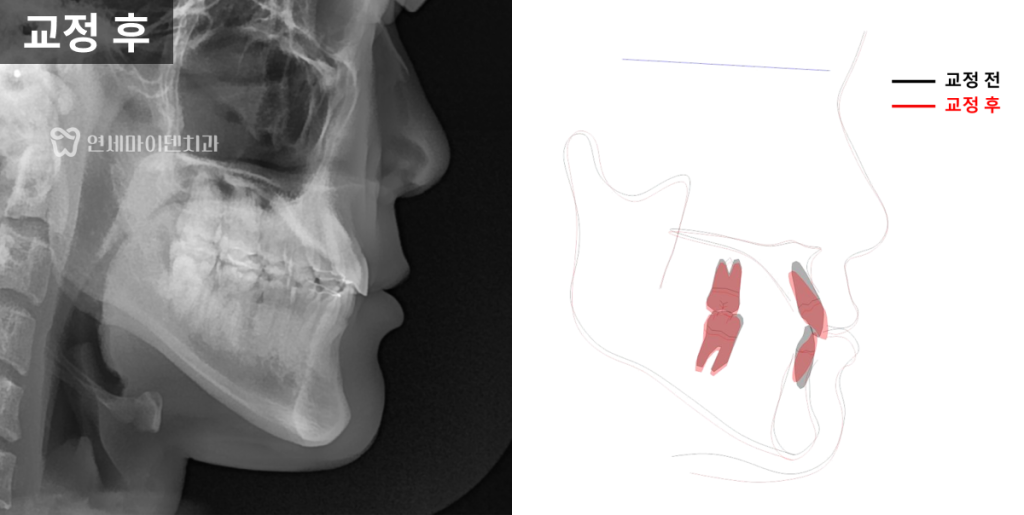

최종 치료 결과

최종적으로

위아래 치아는 가지런하게 배열되었고,

옆모습에서는

턱끝의 돌출이 완화되어

전체적으로 부드러운 인상을

확인할 수 있었습니다.

이는 교정을 통해

교합과 악궁이 변화하면서

턱 위치가 약간 아래쪽으로 회전해

나타난 효과입니다.

전체 치료 기간은

약 2년이 소요되었으며,

파노라마 방사선에서도

치근 흡수나 잇몸 손상 없이

안정적으로 마무리되었습니다.